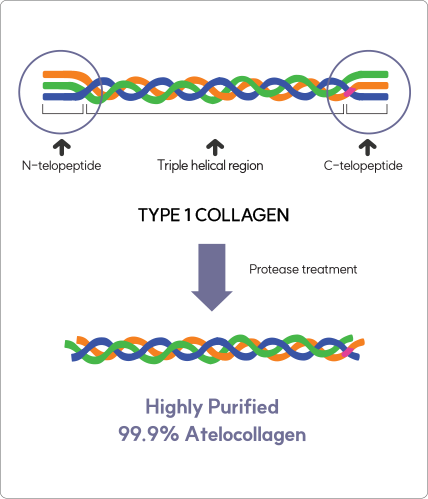

70% of Collagen Structure

Glycine, proline, and lysine account for approximately 70%

of the collagen structure. During fibroblast metabolic activity,

these amino acids stimulate fibroblasts to promote collagen

production and support collagen synthesis, helping improve

skin firmness and structural integrity.